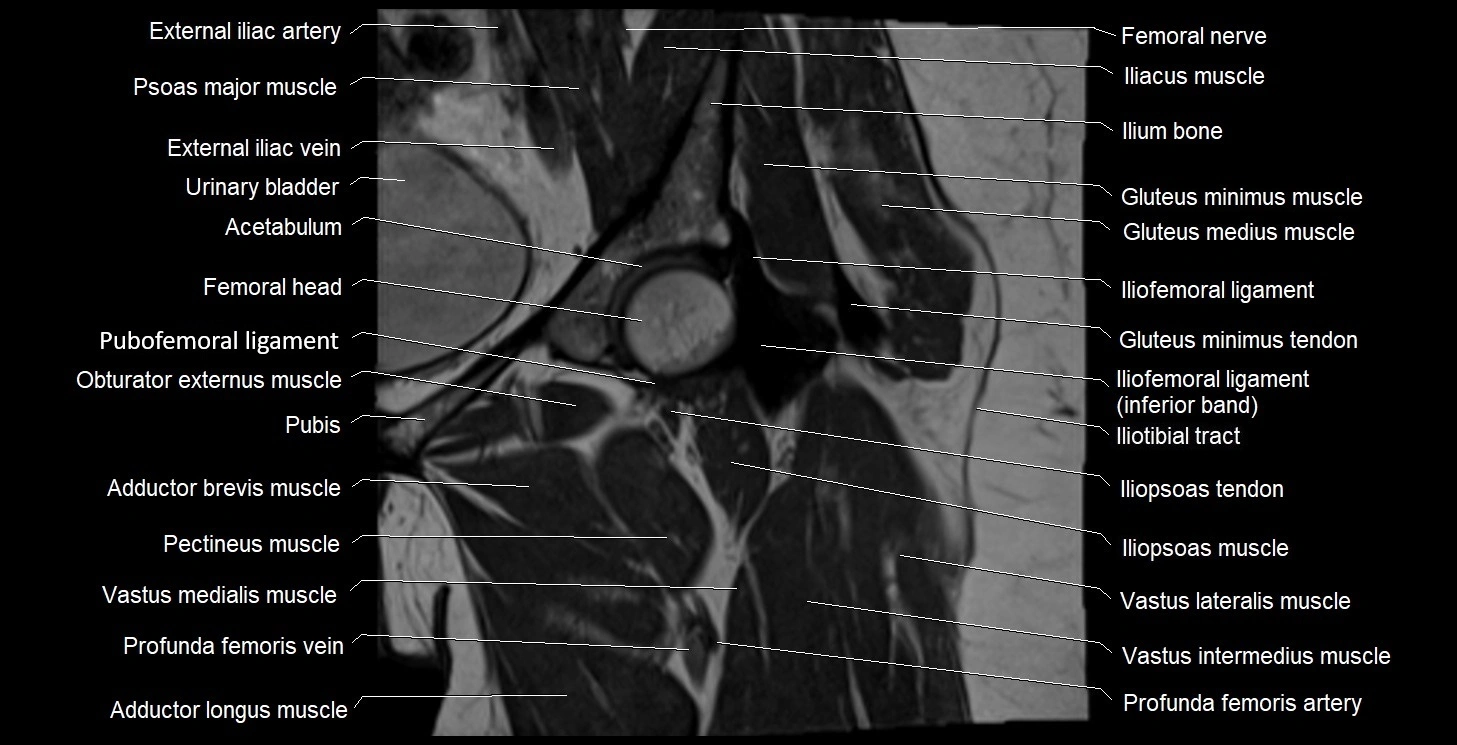

- Acetabulum

- Head of femur

- Iliofemoral ligament

- Iliopsoas muscle

- Iliopsoas tendon

- Iliotibial tract

- Neck of femur

- Psoas major muscle

- Pubofemoral ligament

- Rectus femoris muscle

- Urinary bladder

- Vastus intermedius muscle

- Vastus lateralis muscle

- Vastus medialis muscle